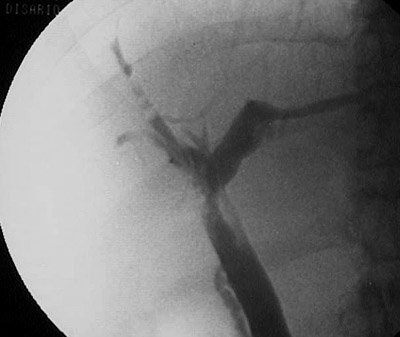

![]() | The cholangiogram views seen here demonstrate a beaded pattern and ductular narrowing and pruning from irregular segmental strictures with fibrosis of bile ducts in a patient with sclerosing cholangitis, an idiopathic fibrous obliteration of extrahepatic and intrahepatic bile ducts. |